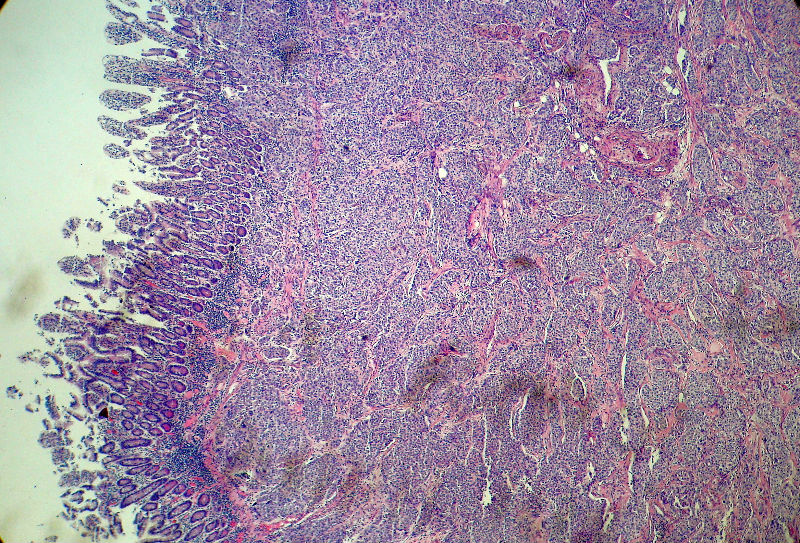

男,82岁,小肠穿孔紧急手术。

大体,小肠一段,长约60厘米,与粘膜面可见三个溃疡型肿物,肠系膜淋巴结肿大。

肿瘤呈巢片状分布,细胞大小相对一致,胞浆丰富,胞核呈细颗粒状,可见小核仁,血管较丰富,考虑神经内分泌肿瘤,加做免疫组化(Ki67、Syn、NSE、CgA、CD56)分级。